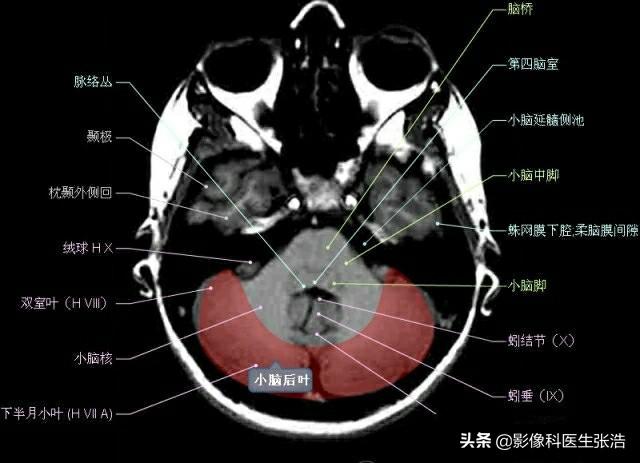

核磁共振(MRI)是一種利用磁場和射頻脈沖來生成身體內(nèi)部結(jié)構(gòu)的詳細(xì)圖像的非侵入性檢查技術(shù),頭部核磁共振主要用于檢查腦部疾病、神經(jīng)系統(tǒng)問題以及血管狀況等,這項(xiàng)檢查對于疾病的早期發(fā)現(xiàn)和治療具有非常重要的意義。